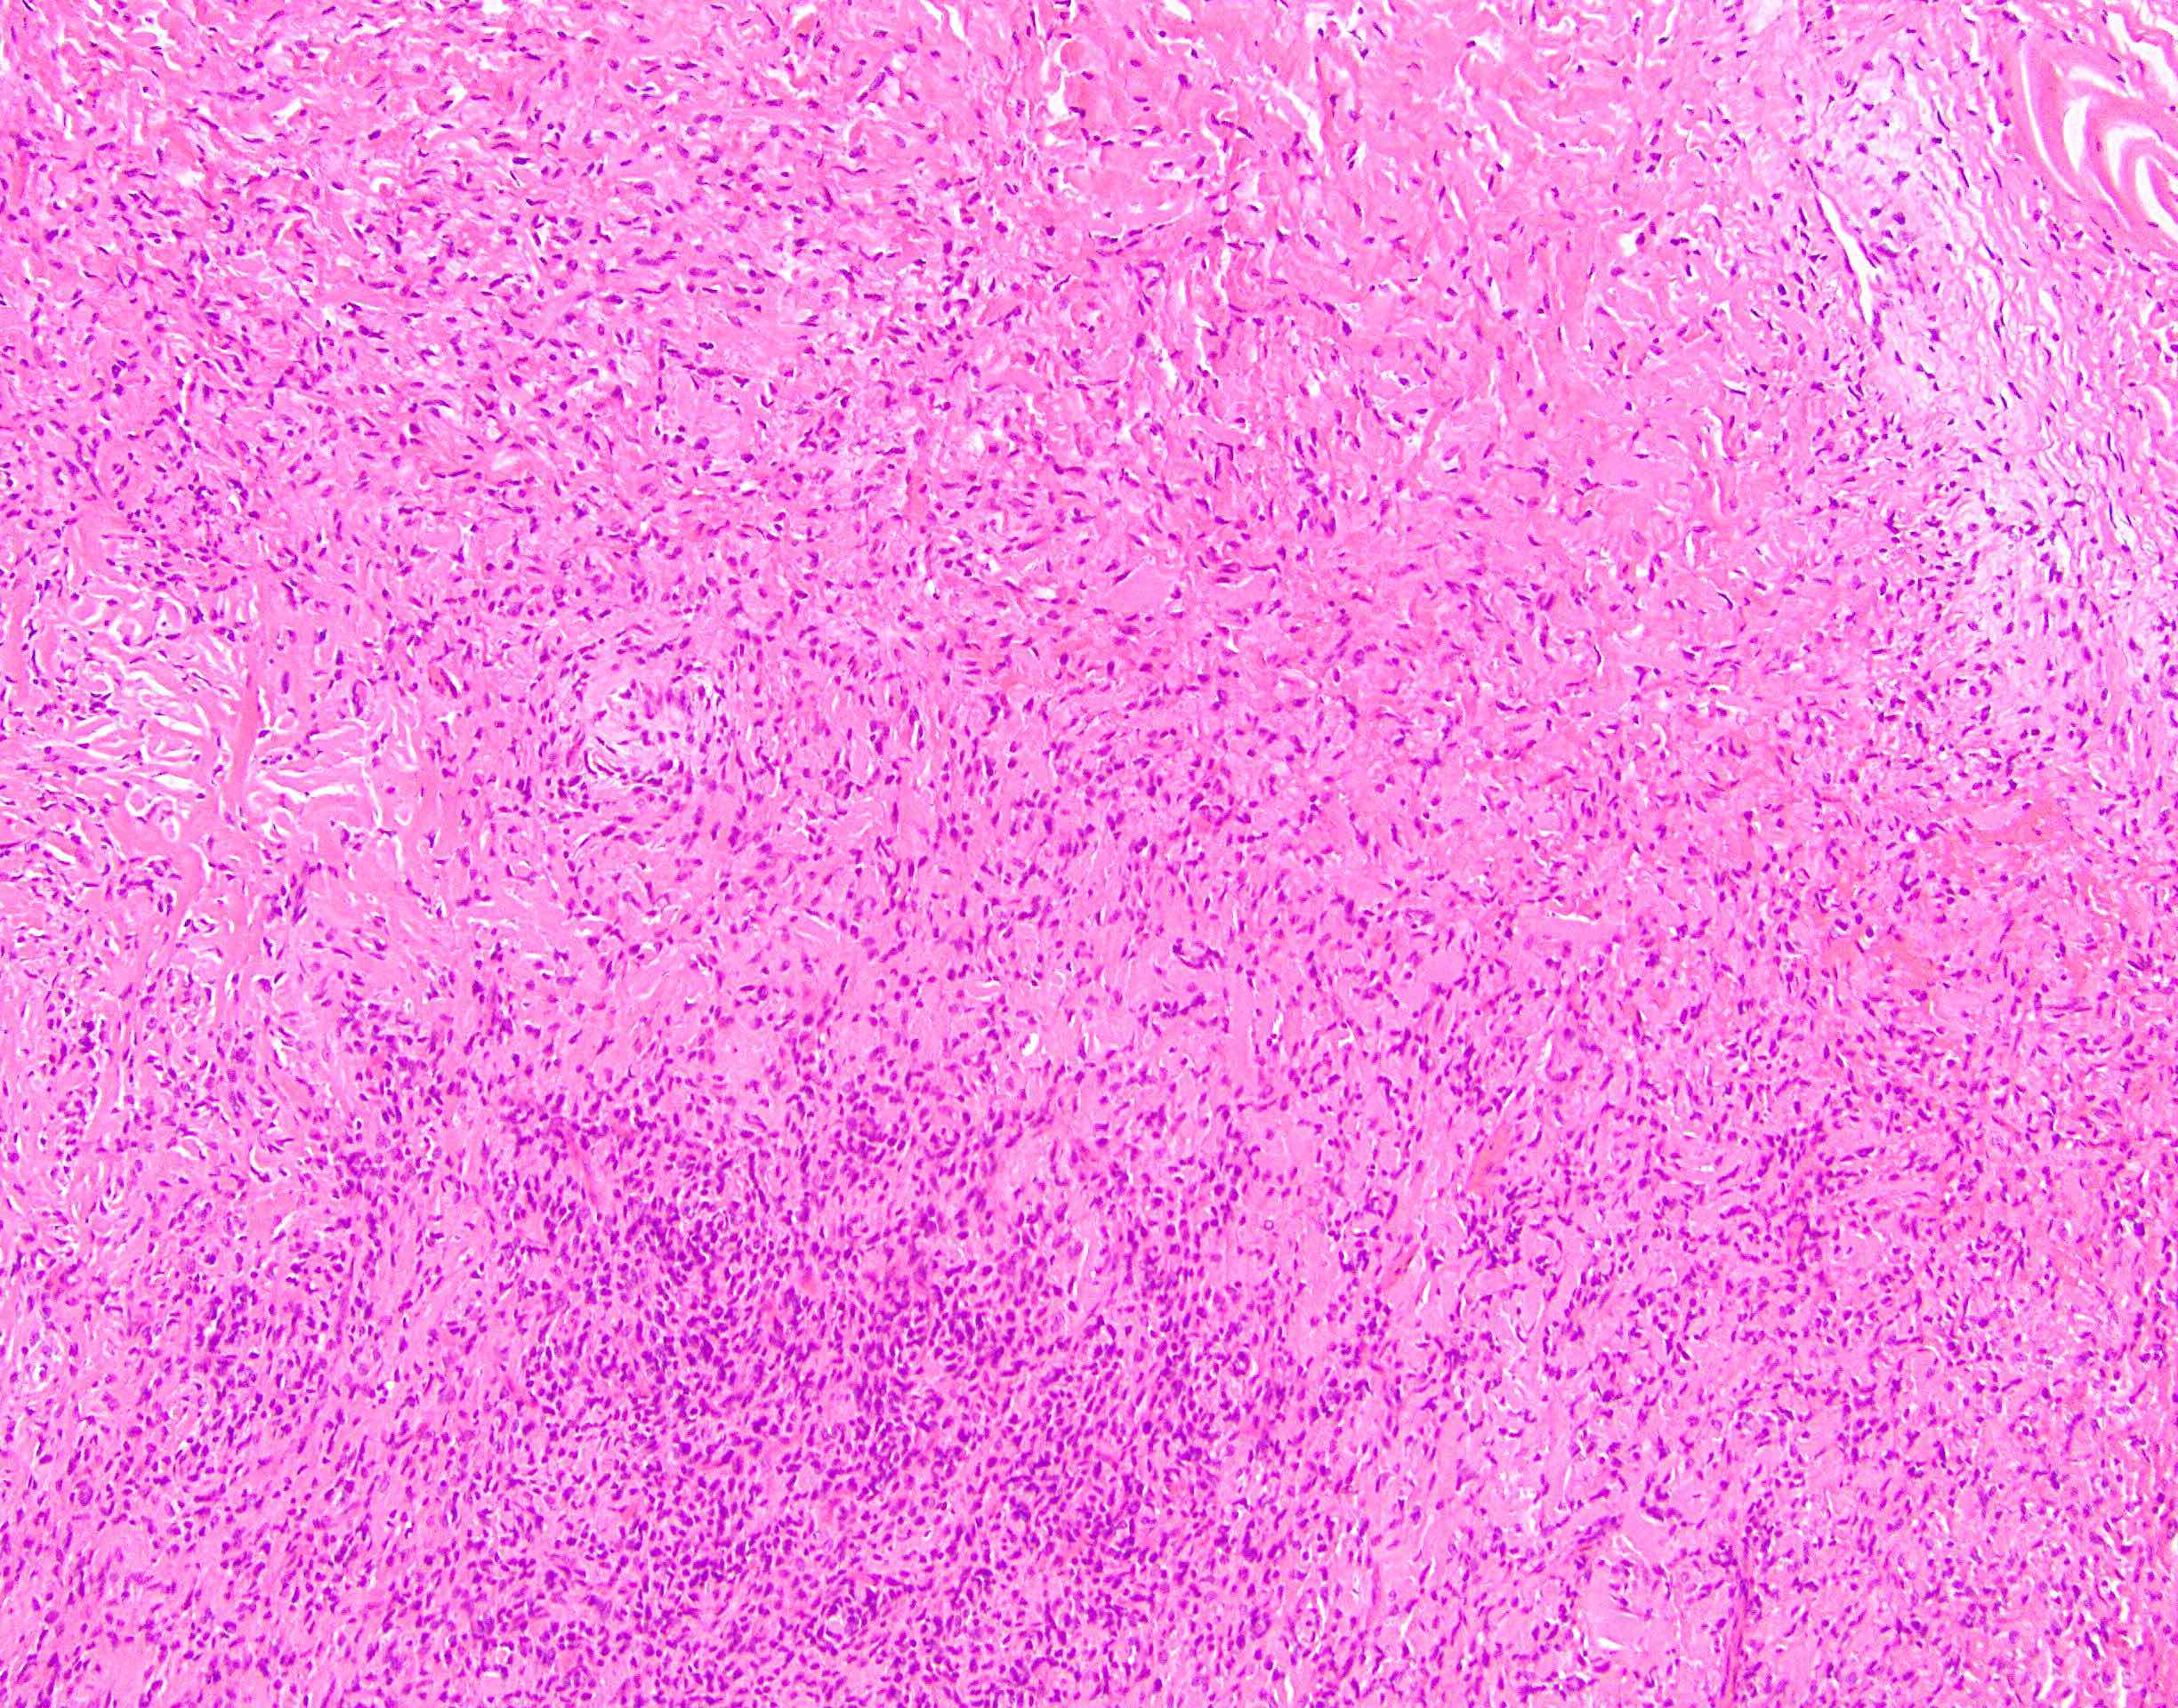

Microscopic (histologic) description

- Low to moderately cellular, bland fusiform or spindled cells with focal to diffuse whirling in heavily collagenized stroma with abrupt transition to myxoid areas

- 45% have epithelioid areas

- 40% contain poorly formed but large collagen rosettes

- Often infiltrates adjacent skeletal muscle

- Occasionally has areas of increased cellularity, atypia, necrosis or mitotic activity characteristic of intermediate to high grade sarcoma

- Recurrences may show increased cellularity and mitotic activity

Microscopic (histologic) images